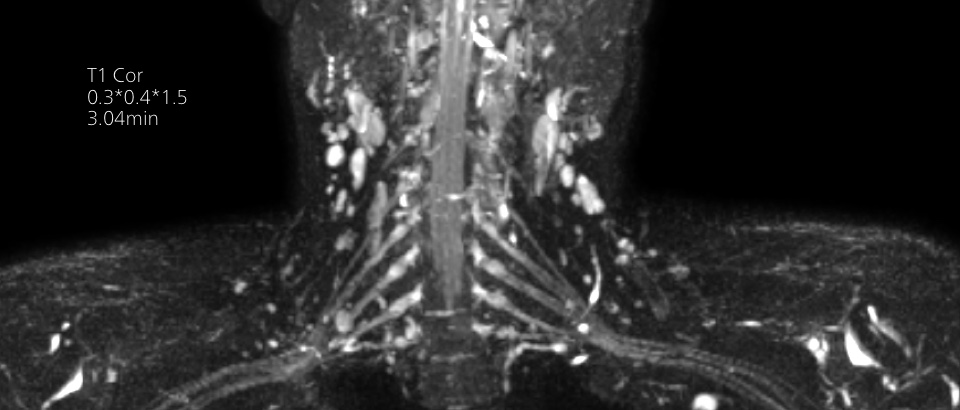

Our lightest Breeze coils bring versatility and create consistent high quality images for any anatomy.

Quality images for quality diagnoses

Our lightest Breeze coils bring extraordinary versatility to imaging challenging anatomies and the smallest joints. A large 55cm field-of-view and premium SNR add to the exceptional image quality.